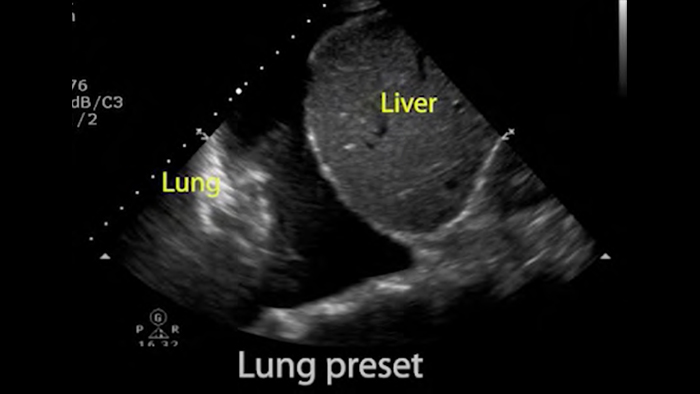

• Rango extendido de frecuencias de operación de 4 a 1 MHz • 2D, Doppler a color, Modalidad M, XRES avanzado e imágenes armónicas multivariables • Imagenología de alta resolución para aplicaciones abdominales y cardíacas: optimizaciones de preajustes de imágenes cardíacas, gineco-obstétricas, pulmonares, abdominales y FAST.

Desde revelar los detalles sutiles de una imagen hasta descubrir la definición del tejido enriquecido desde múltiples ángulos, Lumify puede ayudarlo a tomar decisiones en tiempo real con más confianza desde la evaluación hasta la recuperación.